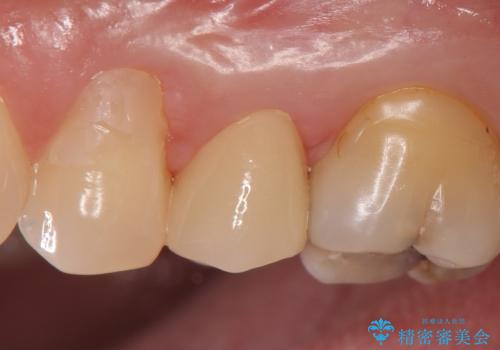

頬側の樹脂及び銀歯を除去後、オールセラミッククラウンにて補綴を行いました。

今回用いたオールセラミッククラウンはジルコニアフレームという白い素材の上にセラミックを盛っているため、審美性が非常に高いのが特徴です。

また、ジルコニアは人工ダイヤモンドの材料にも使われているほど高い強度を持っており、そのためオールセラミッククラウンは審美性だけでなく、奥歯やブリッジの補綴も可能とするクラウンです。